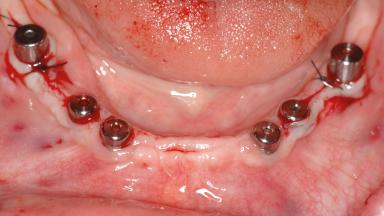

# of Implants 14

Bone Augmentation Horizontal|Sinus Floor Elevation|Staged|Vertical

Augmentation Materials Autogenous chips|Autogenous block(s)|Xenogenous|Membrane

Defining Characteristics Fully edentulous upper jaw to be rehabilitated with four or more implants

Modality Fixed hybrid bridge on 5+ implants

Bone Volume Deficient vertically or deficient vertically AND horizontally